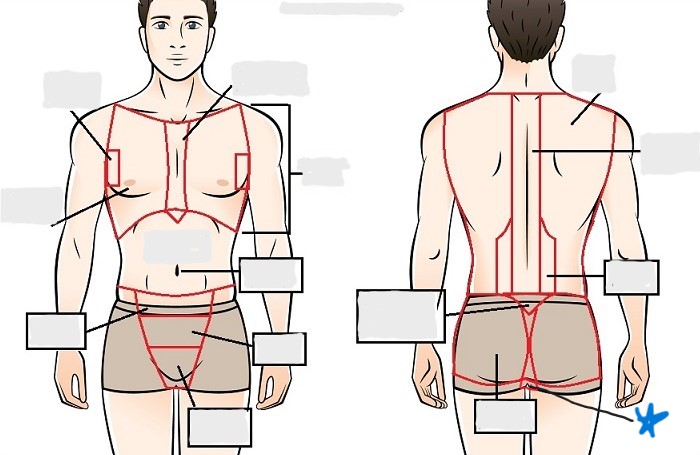

axial

appendicular